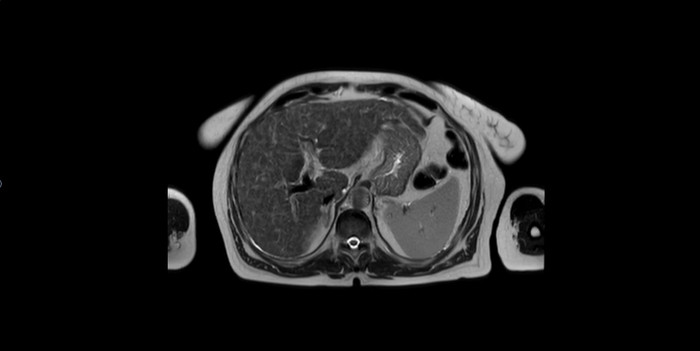

МРТ ОБП возрастной пациентки.

Печень не увеличена: максимальный вертикальный размер правой доли по среднеключичной линии - 150мм (норма до 150 мм), левой доли - 57мм (норма до 100 мм). Контуры печени выражено неровные, бугристые. МР- сигнал от паренхимы печени диффузно неоднородный за счет цирротической трансформации, без убедительной визуализации на этом фоне очаговых образований в структуре. Внутри- и внепеченочные желчные протоки не расширены. Ворота печени дифференцированы. Заключение: Цирротическая трансформация печени

1.Прямые признаки цирроза на МРТ

Морфологические изменения печени:

• Узловая деформация контура – печень становится бугристой (макроузловой или микроузловой цирроз).

• Уменьшение размеров правой доли и хвостатой доли (при прогрессировании).

• Увеличение левой доли (компенсаторная гипертрофия).

• Неоднородная структура паренхимы за счет фиброзных узлов и участков регенерации.

2. Косвенные признаки цирроза на МРТ

Признаки портальной гипертензии:

• Расширение воротной вены (>13 мм) и селезеночной вены.

• Спленомегалия (увеличение селезенки).

• Портокавальные коллатерали (варикозное расширение вен пищевода, желудка, геморроидальных вен).

• Асцит (свободная жидкость в брюшной полости).